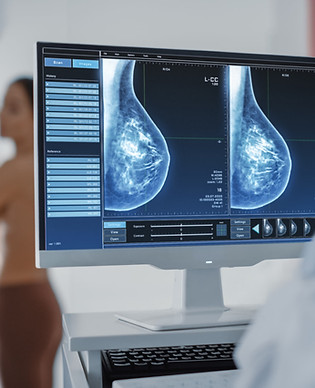

MAMMOGRAPHIE

Bilan sénologique

Mammographie et/ou échographie, interrogatoire et examen clinique des seins.

Dépistage du cancer du sein chez la femme asymptomatique.

Bilan d’une anomalie du sein chez la femme ou chez l’homme.

Les résultats vous sont expliqués le jour-même.

Mammotest

Dépistage du cancer du sein chez la femme asymptomatique, de 50 à 69 ans.

Sur prescription ou sur invitation du Centre de Coordination et de Référence pour le dépistage des cancers (CCRef).

Les résultats sont transmis à votre médecin traitant ou gynécologue traitant par le CCRef.

La mammographie permet d’analyser les seins à l’aide de rayons X.

La tomosynthèse est une technique de mammographie en 3D.

La mammographie est souvent couplée à une échographie des seins qui utilise les ultrasons.